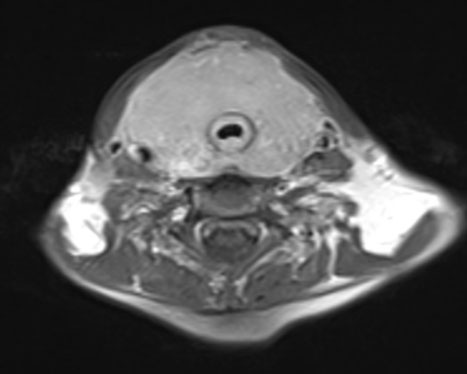

Fourteen years later, the patient presented to our institution with a palpable cervical mass. A total body CT revealed a non-enhancing diffusely enlarged hypodense thyroid gland without the presence of enlarged lymph nodes or other significant abnormalities (Figure 3). A magnetic resonance (MR) examination of the neck done one month later showed a rapid increase in size of the thyroid gland demonstrating diffuse enhancement postgadolinium administration and restricted diffusion. It showed to exert mass effect on the surrounding structures and significant narrowing of the airways. No pathological lymph nodes were seen (Figure 4, Figure 5, Figure 6). Because of the patient’s previous history of lymphoma and rapid growth of the thyroid gland, the possibility of extra-nodal thyroid lymphoma recurrence was raised, and a core needle biopsy of the thyroid gland was done and sent to pathology which confirmed the presence of diffuse large B-cell lymphoma within the thyroid gland.

Figure 4: Axial T1 with gadolinium MR image (2025) showing a rapid increase in size of the thyroid gland with mass effect on the surrounding structures and significant narrowing of the airways.

Figure 5: Axial T2 MR image (2025) showing a diffusely enlarged heterogeneous thyroid gland with mass effect on the surrounding structures and significant narrowing of the airways.